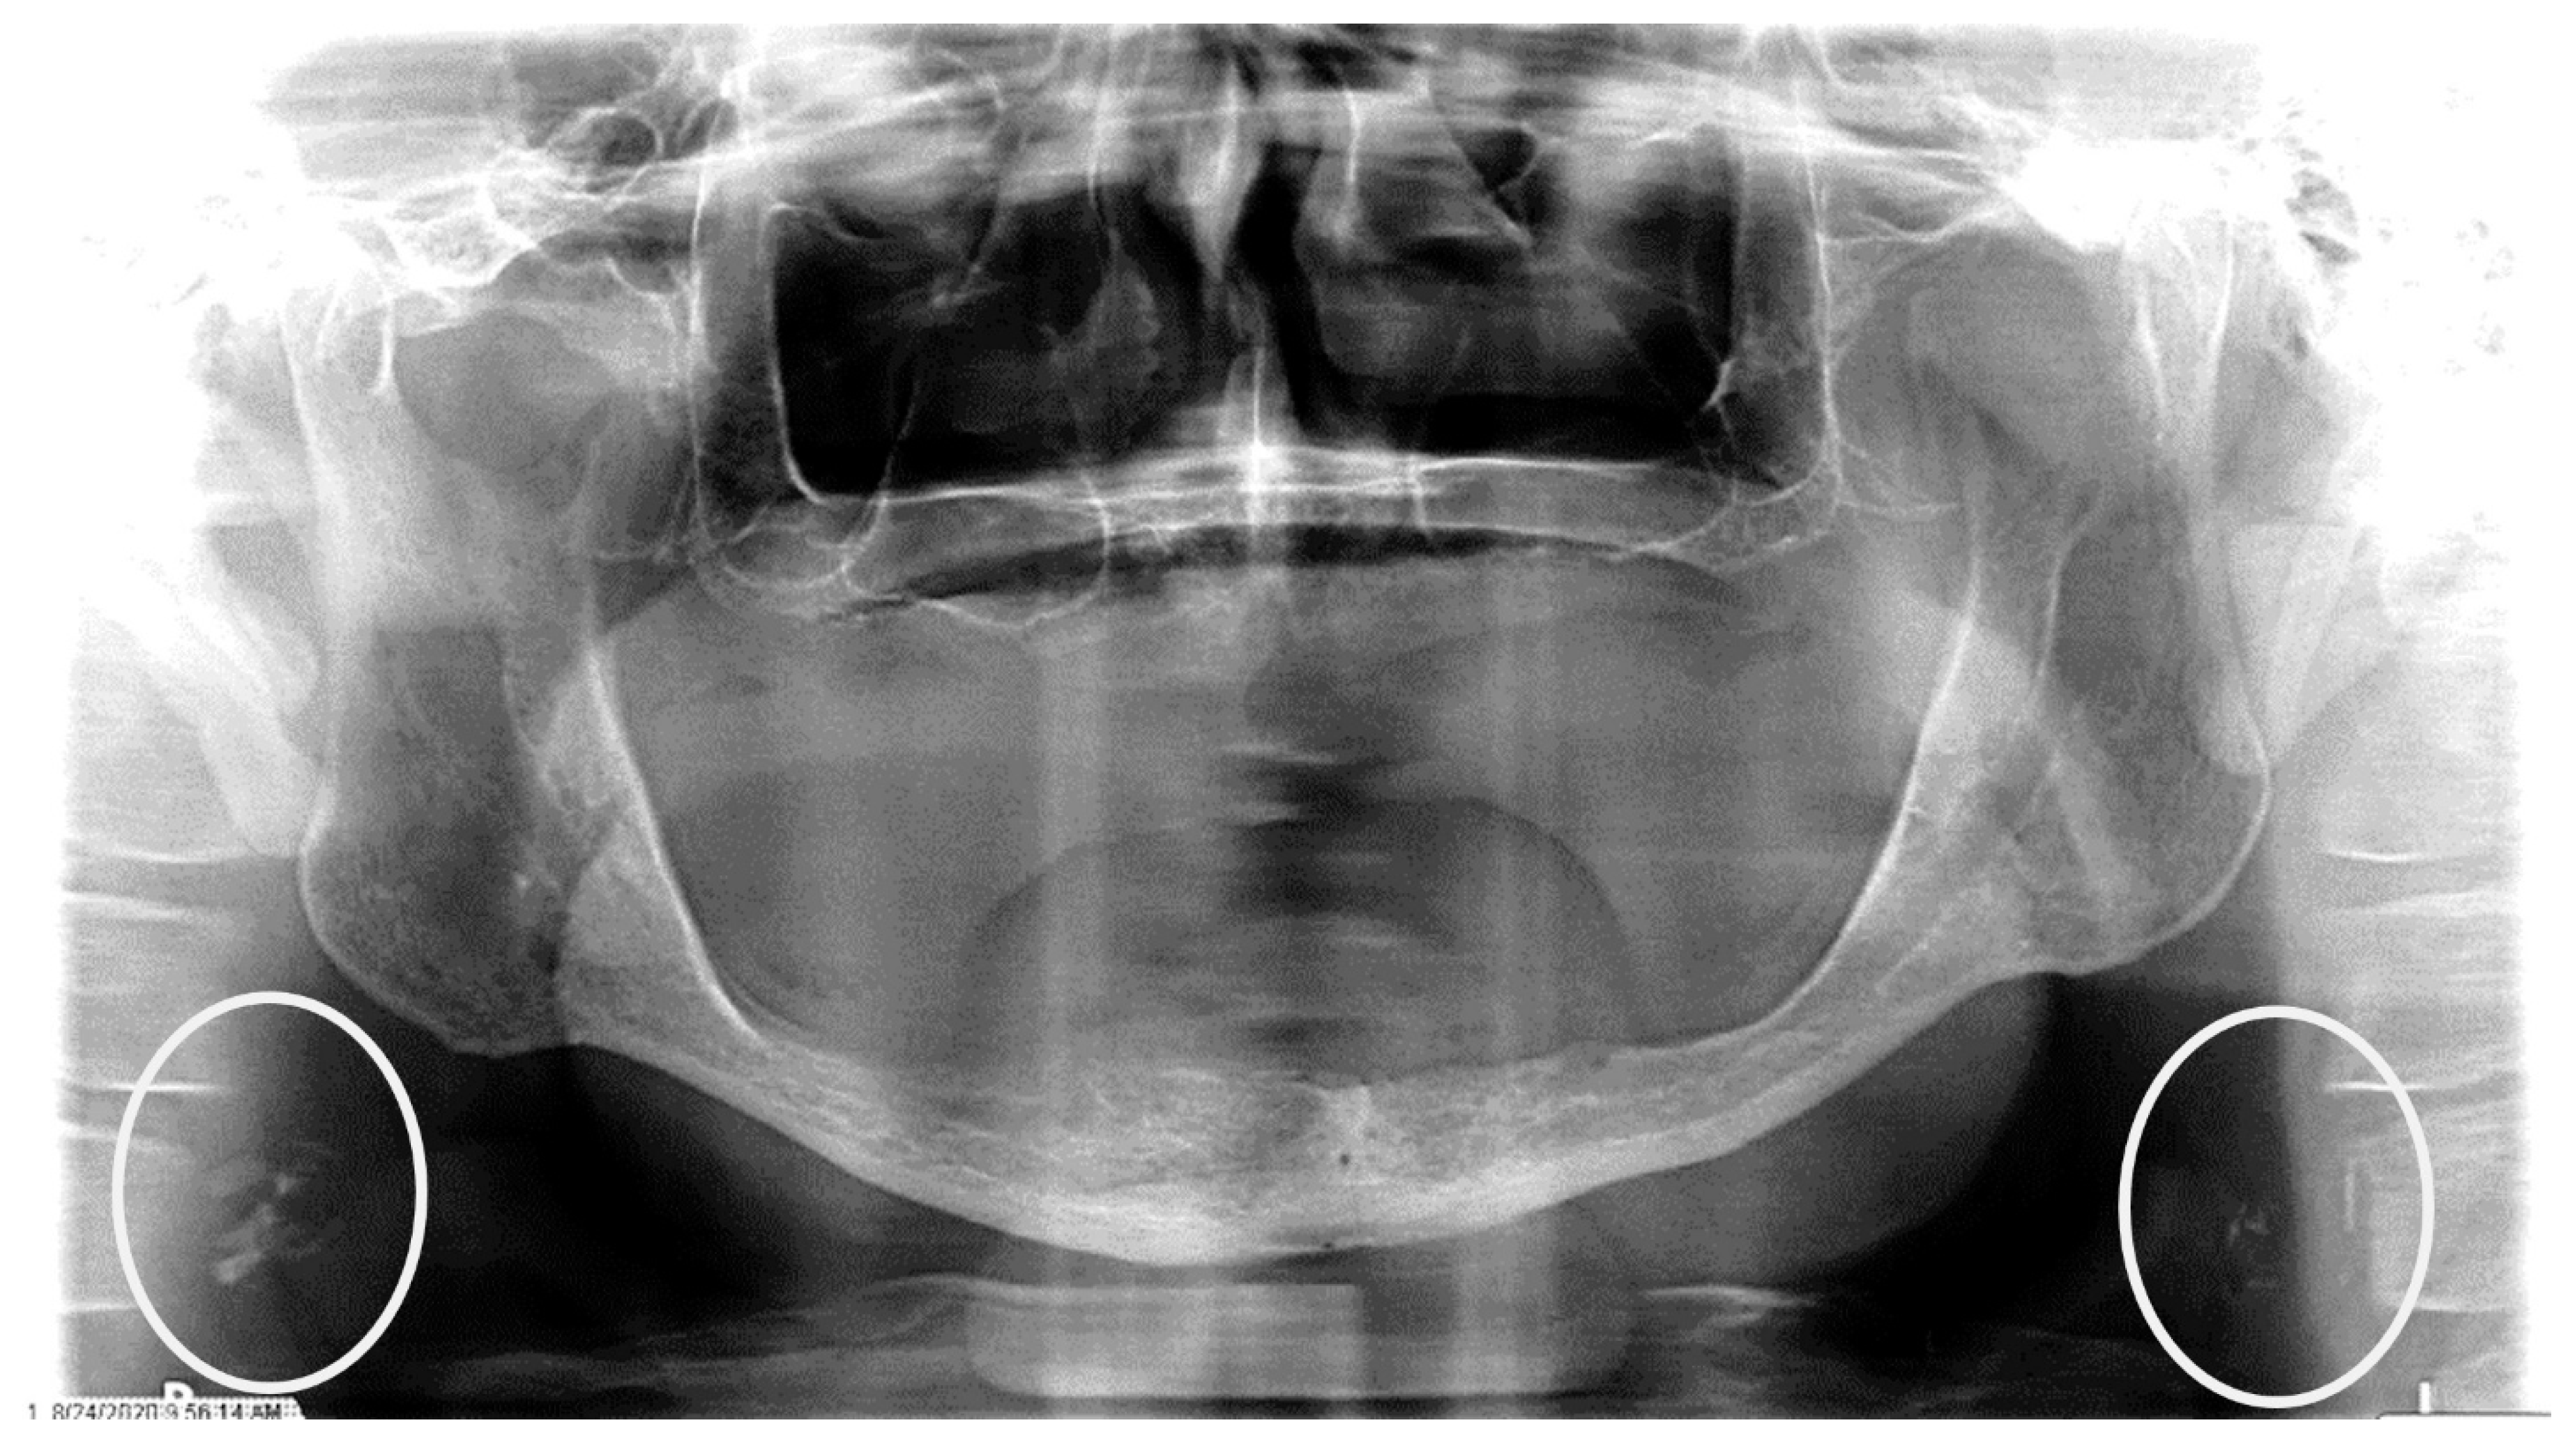

Figure 3.

The panoramic radiograph of an 80-year-old male patient with a medical history of hyperlipidemia and diabetes mellitus showing bilateral carotid artery calcifications (CACs) during a comprehensive dental examination. The CACs are encircled by a white line.

The characteristics of the CAC patients are presented in Table 1. Between 2014 and 2023, there were 559 patient records with the terms “carotid artery calcification” or “carotid” or “calcification of the carotid artery” noted. After the panoramic radiographs were reviewed, 314 patients were confirmed to have a diagnosis of CAC (including 26 patients with a history of carotid endarterectomy). The remaining 245 patient records were excluded because of the absence of detectable CAC on PRs and the absence of PRs to review. The ages ranged from 29 to 92 years, with a median of 68 years. CAC was most prevalent (39.5%) in the seventh decade of life. There were 168 (53.5%) female and 146 (46.5%) male patients. The median age of the female patients was 68 years, and the median age of the male patients was 69.5 years. The calcifications were identified unilaterally in 168 (53.5%) patients (88 females/80 males; mean age: 67.8 years) (Figure 1 and Figure 2) and bilaterally in 146 (46.5%) patients (80 females/66 males; mean age: 68.6 years) (Figure 3, Figure 4 and Figure 5). The DMFT index in the CAC patients ranged from 8 to 32 (mean = 26.6). The frequency of patients with CAC with a history of hypertension, hyperlipidemia, diabetes mellitus, CVA, and CAD was 86.2%, 57.6%, 30.7%, 15.5%, and 28.7%, respectively.